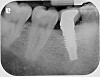

Fig 13. Radiograph depicting peri-implantitis.

Figure 13

Fig 16. Radiograph depicting closed contact at time of implant insertion.

Figure 16

Fig 17. Open proximal contact between implant and adjacent tooth 3 years post insertion.

Figure 17